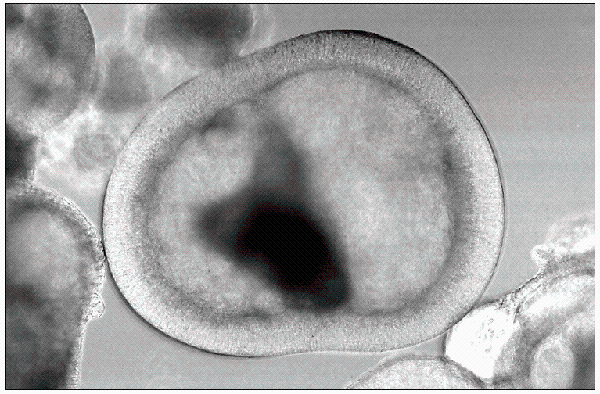

Ein menschlicher Embryo im Frühstadium – entnimmt man daraus Stammzellen, wird der Embryo zerstört. Photo: dpa